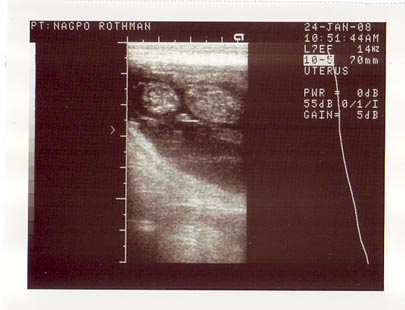

See the puppy? Ya. Well, even if you were there, it was difficult. The beating heart, however, was very apparent. As was the next. And the next. In the image above, the smaller circle on the left is the head. The large circle on the right is the body. The tiny comma-on-its-side shape in between is the heart. The beating heart. The beating heart of a – as of now – live puppy. There was another. And another. Three beating hearts!